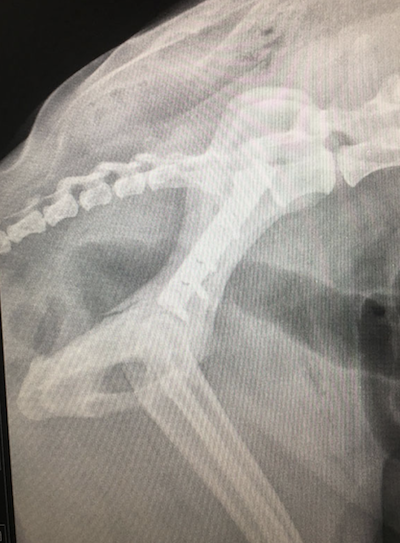

Y Fracture Repair

In a Springer Spaniel.